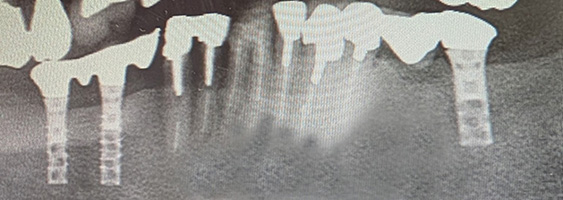

それから32年、現在も1mmの骨吸収もなく、何の問題もなく安定して今日まで機能し続けており当院にとって歴史的な症例となりました。チタンインプラントの信頼性が証明されました。

26年経過症例 / 80歳(2025年現在)・女性

1999年 埋入(54歳)